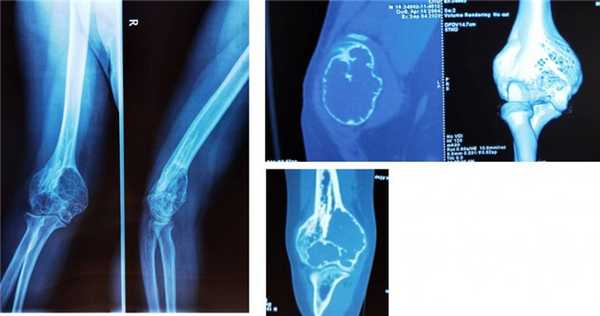

При локализации аневризмальной кисты в метафизах длинных трубчатых костей одновременно с болью появляется припухлость, болезненная при пальпации, повышение местной температуры.

Так же очень часто при аневризмальной кисте кости наблюдаются патологические переломы кости. В некоторых случаях они являются причиной выявления кист.

Встречается реже солитарной. Обычно возникает у девочек 10-15 лет. Может поражать кости таза и позвонки, реже страдают метафизы длинных трубчатых костей. В отличие от солитарной костной кисты, как правило, возникает после травмы. Формирование полости сопровождается интенсивными болями и прогрессирующим отеком пораженной области. При осмотре выявляется местная гипертермия и расширение подкожных вен. При локализации в костях нижних конечностей отмечается нарушение опоры. Заболевание нередко сопровождается развитием контрактуры близлежащего сустава. При костных кистах в позвонках появляются неврологические нарушения, обусловленные сдавление спинномозговых корешков.

Различают две формы аневризмальных костных кист: центральную и эксцентрическую. В течении болезни выделяют такие же фазы, как и при солитарных кистах. Клинические проявления достигают максимума в фазе остеолиза, постепенно уменьшаются в фазе отграничения и исчезают в фазе восстановления. На рентгенограммах в фазе остеолиза выявляется бесструктурный очаг с внекостным и внутрикостным компонентом, при эксцентричных кистах внекостная часть по размеру превышает внутрикостную. Надкостница всегда сохранена. В фазе отграничения между внутрикостной зоной и здоровой костью образуется участок склероза, а внекостная зона уплотняется и уменьшается в размере. В фазе восстановления на рентгенограммах обнаруживается участок гиперостоза или остаточная полость.